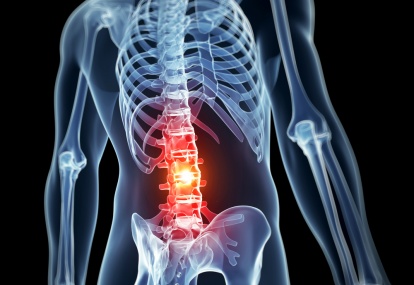

Management of malignant spinal cord compression

Metastatic or malignant spinal cord compression (MSCC) is defined as spinal cord or cauda equina compression by direct pressure and/or induction of vertebral collapse or instability by metastatic spread or direct extension of malignancy that threatens or causes neurological disability.1 MSCC is a neurological...